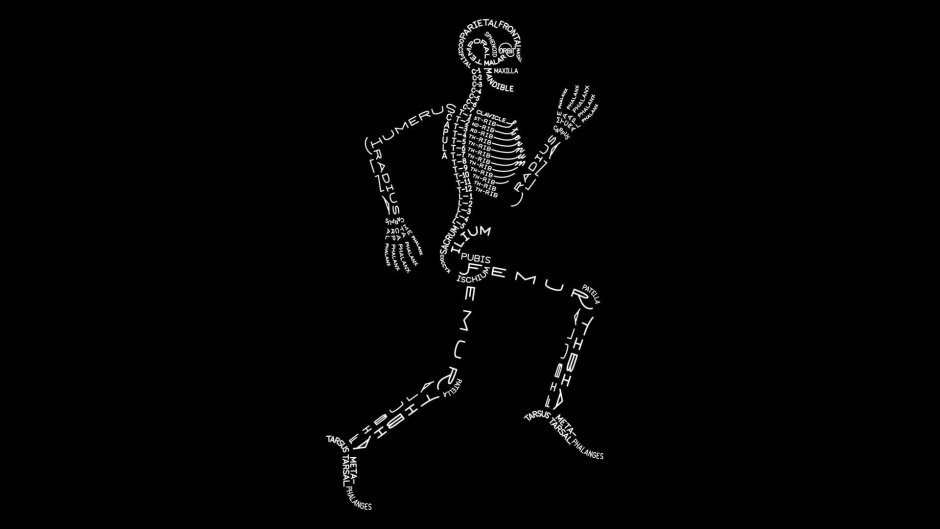

9. Скелет на черном фоне

26. Анатомия Минимализм

54. Скелет Минимализм